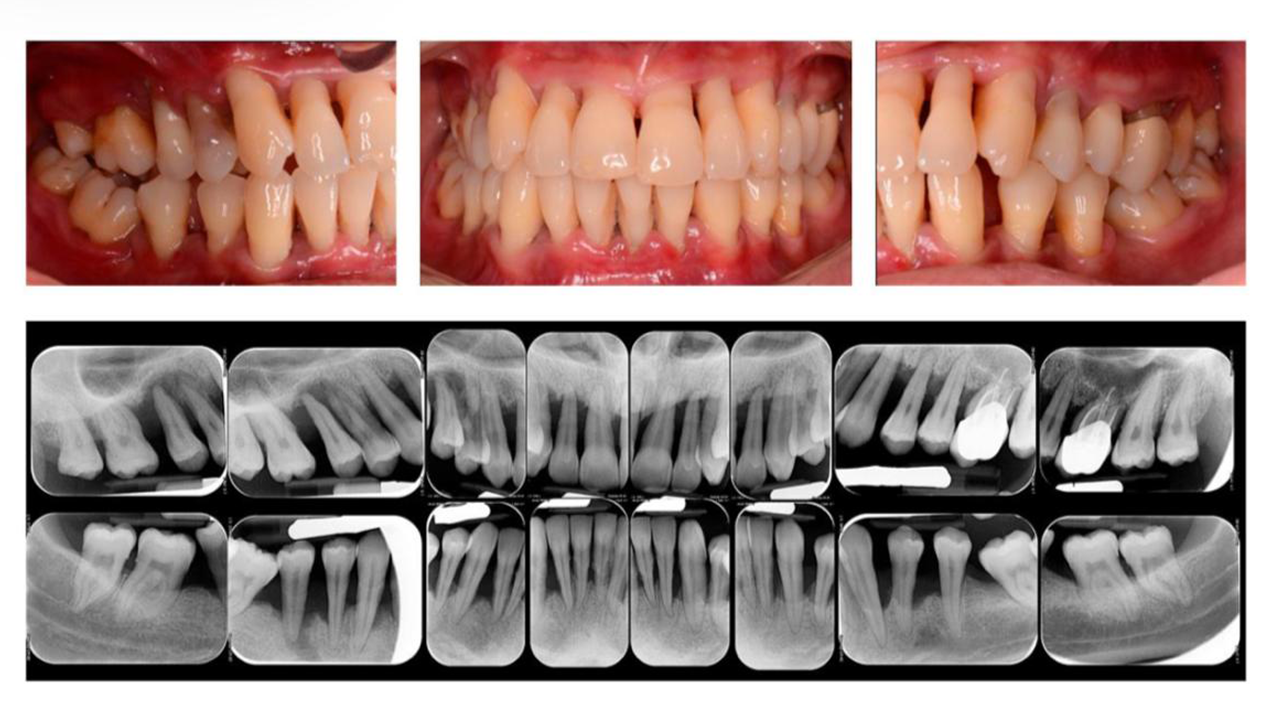

2. Periodontitis (Gambar 3). Periodontitis bersifat kronis dan progresif, serta dapat menyebabkan mobilitas hingga kehilangan gigi jika tidak mendapatkan perawatan yang berkelanjutan (1,4,5,6)

Gambar 3. Periodontitis (Peradangan pada jaringan penyangga gigi)5